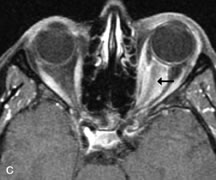

PATIENT PREPARATION Before MRI is performed, patients must be screened and prepared to avoid the potential hazards associated with the strong magnetic field. Patients who have ferrous aneurysm clips or cardiac pacemakers, who depend on life-support equipment, or who retain a possible metallic intraocular foreign body are not candidates for this imaging modality. MRI cannot be performed on obese patients who cannot fit into the bore of the magnet. Patients who are claustrophobic may not tolerate a prolonged period of study within the confines of the magnet, whereas others might do well if given a mild sedative. All worn metallic objects (e.g., necklaces, watches) should be taken off, credit cards set aside, and eye makeup removed before entering the room containing the magnet.5,20,34,35,36 NORMAL ORBITAL ANATOMY T1-weighted images provide the best anatomic details of the orbit because they display superior contrast resolution between normal structures (see Fig. 8). The vitreous has a long T1, resulting in an intermediate signal similar to brain, whereas the crystalline lens and sclera appear dark because of a longer T1 and short T2. The extraocular muscles, like all skeletal muscles, demonstrate a moderately long T1 and short T2 and highly contrast with the intense signal of the surrounding orbital fat (adipose tissue has an extremely short T1). The lacrimal glands appear as mottled areas of reduced intensity of the signal from the orbital fat in the lacrimal fossa. The optic nerves are seen with the same signal intensity as brain white matter and are hypointense relative to the orbital fat because their Tl is longer than the Tl of fat but shorter than the Tl of water. Cortical bone is not well delineated because it contains little free water, yielding minimal signal in MRI, and thus appears dark on all pulse sequences. This feature explains why MR images of the orbital apex and intracanalicular portion of the optic nerves are superior to comparable CT scans. Partial volume averaging of the bones in these regions obscures soft tissue details on CT images, whereas MRI reveals the signals only from the soft tissue structures with no cortical bone input. Bone marrow, on the other hand, is seen as a relatively intense signal because of its high fat content (see Fig. 8).37,38 T2-weighted pulse sequences are not ideal for imaging normal anatomy; however, they are particularly useful in revealing pathologic conditions (see Fig. 9). T2-weighted studies are most easily recognized by a bright vitreous signal. ORBITAL DISEASES Vascular Lesions Cavernous hemangiomas appear as well-circumscribed, smooth, usually intraconal masses that are isointense to muscle on T1-weighted images and hyperintense on T2-weighted images (Fig. 12). Patchy early enhancement is typically followed by diffuse, more homogeneous enhancement.39 The internal architecture of the mass, including septation and internal vasculature, may often be appreciated with high-quality orbital imaging.40 Lymphangiomas consist of ectatic vascular channels within a connective tissue stoma with varying degrees of lymphoid cellularity. On MRI, these tumors are typically poorly circumscribed, multicompartmental, and heterogeneous, often showing cystic dilations with fluid levels (Fig. 13). The signal characteristics within lymphangiomas vary considerably, reflecting cystic and solid components and the varying paramagnetic characteristics of blood at different stages of degradation.40–42 Acute hemorrhage appears hypointense on both T1- and T2-weighted formats. Methemoglobin present in subacute hemorrhage (3 to 14 days) leads to hyperintense signal on both T1- and T2-weighted images.41 A small percentage of lymphangiomas appear radiologically indistinct from orbital cavernous hemangiomas.43 Orbital varices are venous malformations that expand with increased systemic venous pressure, such as with Valsalva maneuvers. Because rapid acquisition of images during a Valsalva maneuver is important in imaging such a lesion, conventional or spiral CT is currently the modality of choice.44 MRI is an excellent modality for demonstrating enlargement of the cavernous sinus and dilation of the superior ophthalmic vein in patients with high-flow carotid-cavernous fistulas (Fig. 14).37MRA may be helpful in the evaluation of the venous outflow pattern. The rapidly flowing blood in these vascular structures carries the excited protons out of the section before they can be imaged, resulting in their dark appearance.5 In low-flow dural arteriovenous malformations, MRA may help define the arterial feeding vessels.45 Neural Lesions MRI is more effective than CT in delineating the intracranial optic nerves, chiasm, and optic tracts and, for this reason, is the preferred imaging modality in the evaluation of optic nerve disorders. The spatial relationships and image contrast of the orbital tissues with intraorbital optic nerve tumors is comparable between the two imaging modalities. The normal nerve is isointense to brain and appears enlarged and kinked owing to infiltration of an optic nerve glioma on T1-weighted images. Gliomas appear hyperintense on T2-weighted images and may be heterogeneous owing to cystic areas within the tumor. Contrast enhancement is variable.46 Intraorbital and intracranial optic nerve sheath meningiomas are usually isointense to cortical gray matter on Tl-weighted images and remain isointense on proton density studies (Fig. 15). Gd-DTPA is useful in delineating the intracranial extension of optic nerve meningiomas.7,47 The hyperostosis of bone and calcification associated with meningiomas are not demonstrated as well on MRI studies as on CT scans.20,37 Gd-DTPA–enhanced MRI also appears promising in the study of the permeability of the blood–brain barrier in selected optic neuropathies.22,48 MRI may reveal an enlarged optic nerve and some degree of contrast enhancement in cases of optic neuritis.49 Muscle Disorders Extraocular muscle enlargement in patients with thyroid-associated orbitopathy is demonstrated equally well with CT and MRI studies. However, the superior tissue contrast on MR images reveals better details of the relationships of the optic nerve to the thickened muscles at the orbital apex (Fig. 16).50 In addition, MRI may be able to differentiate between muscles that are enlarged as a result of edema and active inflammation and those enlarged because of fibrosis by their T2 relaxation times.21 Quantitative MRI was not found to be accurate in predicting the success of low-dose orbital irradiation.51 However, a muscular index relating the diameters of the rectus muscles to the bony orbital dimensions was useful in predicting optic nerve compression.52 MRI is also effective in imaging orbital tumors of mesenchymal origin, such as rhabdomyosarcoma, particularly in the assessment of extension into the anterior and middle cranial fossae (Fig. 17).37 The lack of any pathognomonic radiologic features necessitates rapid orbital biopsy when rhabdomyosarcoma is suspected. Osseous Lesions In general, CT is the imaging modality of choice when details of quantity and quality of bone are needed; however, abnormalities of bones can be detected indirectly by MRI. Cortical bone appears black (signal void) on MR images because of its low proton density and free-water content. The absence or discontinuity of the signal void of the orbital walls may represent bony destruction or fracture. Hyperostosis associated with prostate metastases or meningioma is visualized as areas of black smudging.50,53 Diseases in which the bone is replaced by pathologic tissues with a high free-water content, such as fibrous dysplasia, are well demonstrated on MRI. An intermediate signal intensity on T1-weighted images and hypointense signal on T2-weighted images is representative of fibrous dysplasia. Enhancement on post–Gd-DTPA MR scans is seen and is more evident in areas that are less mineralized.54 Cystic Lesions Dermoid cysts appear as rounded, well-defined lesions typically contiguous with an orbital bony suture. The high-intensity signal on T1-weighted images is attributed to the sebaceous-produced lipid contents (Fig. 18).31,50 Mucoceles may demonstrate a hypointense or hyperintense signal on MR images, depending on the concentration of proteinaceous or inflammatory fluid components. The integrity of the bony walls of the expanded sinus cavities cannot be assessed on MR as well as by CT.37,50,55,56 A high-signal intensity on Tl- and T2-weighted images is characteristic of orbital chronic hematic cysts because of the blood-breakdown products within the cysts.57 Trauma Although soft tissue relationships are usually better demonstrated on MRI, the evaluation of craniofacial bony trauma is preferable with CT. For example, prolapse of orbital fat through a fracture site and hemorrhage of adjacent tissues are demonstrated in an MR image, but the actual fractured bone is not imaged. Three-dimensional MRI of the orbit in subacute trauma has been described,58 although its precise role is not currently established. MRI has been suggested to be superior to CT in detecting intraorbital wooden foreign bodies.59,60 In a series of penetrating orbital injuries with organic foreign bodies, however, MRI was able to identify the foreign body in only four of seven cases.61 With an in vitro model for wood foreign body, McGuckin and colleagues concluded that CT was the imaging modality of choice.62 A careful history and, in selected cases, plain films to rule out a metallic foreign body are crucial before MRI is considered in patients with periocular trauma. MRI is particularly helpful in the detection and characterization of subperiosteal hematomas of the orbit (Fig. 19). They are most commonly seen in the subperiosteal space of the superior orbit as well-defined masses following a traumatic injury. The signal intensity varies depending on the acute, subacute, or chronic nature of the hematoma, based on the stage of blood degradation. Fresh hemorrhages are hypointense on T1-weighted images and hyperintense on T2 images. Hematomas that are 1 to 7 days old are hypointense on both T1- and T2-weighted images. T1-weighted images of hematomas more than a week old are hyperintense due to the oxidation of deoxyhemoglobin to methemoglobin, whereas the T2 images remain hypointense.63 Metastatic Tumors Breast carcinoma metastatic to the orbit has been demonstrated to be hypointense to the surrounding orbital fat on T1-weighted studies and hyperintense on T2-weighted images and has an affinity to the extraocular muscles (Fig. 20).50,64 The MRI characteristics of prostate carcinoma metastatic to the orbit have been described as involving the greater and lesser wing of the sphenoid, orbital roof, and optic canal. Diffuse bone hypertrophy with isointense or slightly hyperintense tissue on T1-weighted images represents the osteoblastic carcinomatous bone infiltration. Contrast enhancement is variable on T1-weighted and fat-suppressed images.65 Most other metastatic tumors also have a lower intensity signal on T1-weighted images and appear to displace or infiltrate normal orbital structures; however, their signal characteristics are variable on T2-weighted MR images.66 Many metastatic tumors demonstrate bright contrast enhancement with Gd-DTPA. Infectious Disorders MRI findings of preseptal and orbital cellulitis typically include increased signal intensities on T2-weighted images of the eyelids and orbital fat, respectively, due to the increased water content of the tissues. Since most cases of bacterial orbital cellulitis are associated with paranasal sinusitis, hyperintense signals of the affected sinuses may also be found on T2-weighted images as well as enhancement of polyps and granulation tissue on postgadolinium T1-weighted MR images. Subperiosteal abscess formation may occur due to contiguous spread of infection from the paranasal sinuses and appear on MRI as an area of intermediate signal on T1-weighted and proton-weighted MR images. The abscess may appear slightly hyperintense compared with muscle on T2-weighted scans with the necrotic contents having the greatest intensity.67 MRI and MRV are more sensitive than CT in revealing cavernous sinus thrombosis. Engorgement of the cavernous sinus, extraocular muscles, and ophthalmic veins is seen with hyperintensity of the thrombosed sinuses evident on all pulse sequences. The enlarged, thrombosed superior ophthalmic vein appears less hypointense than the normal contralateral ophthalmic vein, and hyperintensity within the lumen of the vessel may be seen on T1- and T2-weighted MR images.68 Inflammatory and Lymphoproliferative Lesions Inflammatory conditions of the orbit, both idiopathic (inflammatory pseudotumor) and those of known causes, have been found to be hypointense to fat and isointense to muscle on Tl-weighted studies and isointense or slightly hyperintense to fat on T2-weighted images (Fig. 21).50,64,69 The more fibrous or sclerosing varieties have less signal intensity on T2-weighted images. Marked enhancement is seen in pseudotumor infiltrates after gadolinium administration.70 The same signal characteristics are demonstrated in patients with Tolosa-Hunt syndrome, with mass lesions seen in the cavernous sinuses and orbital apices.71 Lymphomas have MRI characteristics similar to those of inflammatory lesions in that they are hypointense to fat and isointense to muscle on T1-weighted images (Fig. 22). They may appear hyperintense to fat on T2-weighted images, perhaps owing to less fibrosis than that seen in orbital inflammatory pseudotumor, although this is not a consistent finding.31,50,66 Lymphoid tumors typically enhance moderately after contrast injection. Unfortunately, studies have shown that tumor density and homogeneity are similar between inflammatory and malignant orbital infiltrates, and MRI cannot differentiate these lesions.72,73 Lacrimal Gland Tumors Lacrimal gland lesions present special problems in diagnosis and management. Pleomorphic adenoma (benign mixed tumor) should not be biopsied, but rather excised in toto. On the other hand, for lymphoma and inflammatory infiltrates, incisional biopsy is more appropriate than complete excision of the lacrimal gland. Thus, preoperative clinical and radiologic evaluation are especially crucial in planning appropriate surgical management. Pleomorphic adenomas demonstrate long T1 and T2 signal characteristics. They may show heterogeneity on T2-weighted images74 and moderate to marked enhancement with contrast.75 Signal characteristics of adenoid cystic carcinoma include hypointensity to fat on T1-weighted images, hyperintensity to fat with increased T2 weighting, and isointensity to fat on proton density-weighted studies (Fig. 23).31,75 Secondary bony alterations of the lacrimal fossa associated with lacrimal gland tumors, such as remodeling (benign mixed tumor) or destruction (adenoid cystic carcinoma), are seen indirectly on MR images; however, bone windows on CT scans provide better delineation of these changes. In contrast to the round or globular appearance of benign or malignant epithelial tumors of the lacrimal gland, lymphoproliferative tumors usually appear to be molding or draping onto the globe and the surrounding bony orbit. LACRIMAL DRAINAGE SYSTEM DISORDERS MRI with surface coils provides excellent spatial resolution and tissue-specific signal intensities of the lacrimal drainage system. These parameters have been found useful to more accurately demonstrate the extent of lesions in the lacrimal sac and differentiate long-standing mucoceles from solid tumors than CT.76 Physiologic studies in patients with tearing disorders now include MR dacryocystography, in which Gd-DTPA is either placed topically in the conjunctival fornix or injected by cannulation into the lacrimal sac. They provide a detailed morphologic and functional analysis of the lacrimal excretory system; however, they are no more sensitive than digital-subtraction dacryocystography or CT dacryocystography.77–79 INTRAOCULAR TUMORS On MRI, uveal melanomas have a typical appearance that helps to differentiate them from other primary and secondary intraocular tumors as well as choroidal detachments. Pigmented melanomas are hyperintense on Tl-weighted images, hypointense on T2-weighted studies, and hyperintense on proton density–weighted examinations (Fig. 24).30,31,50,80–82 These signal characteristics have been attributed to the paramagnetic properties of melanin because of stable free radicals that shorten the T1 and T2 relaxation times. Moderate enhancement is seen on postgadolinium T2-weighted images. Gadolinium-enhanced T1-weighted images are particularly sensitive in detecting choroidal melanomas.83 MRI may be less sensitive in detecting extrascleral extension of tumor than echography performed by an experienced ultrasonographer.84 Tumors metastatic to the choroid are hyperintense on T1- and T2-weighted images.24 The signal characteristics, however, may be similar to those seen with choroidal melanoma. Choroidal hemangiomas, on the other hand, have an intermediate signal on T1-weighted sequences and become hyperintense on T2-weighted images50 as well as proton density–weighted images.81 Retinoblastomas display moderate signal intensity on T1-weighted studies and a low signal on T2-weighted images.31,80,85 Calcification can be easily detected by CT and ocular ultrasonography but is not imaged by MRI.25,50 The presence of optic nerve involvement is best evaluated by MRI. ACQUIRED ANOPHTHALMIA When an eye is removed owing to tumor or trauma, an implant is typically placed in the intraconal space. MRI may be useful in defining the size, shape, and position of such orbital implants.86 Porous hydroxyapatite or polyethylene implants are preferred by many surgeons performing enucleation or evisceration. A porous implant offers the possibility of supporting a motility coupling peg to increase the movement of the overlying prosthesis. MRI with contrast is used by some surgeons to evaluate the degree of fibrovascular ingrowth in hydroxyapatite87 and porous polyethylene88 implants prior to motility peg placement. |